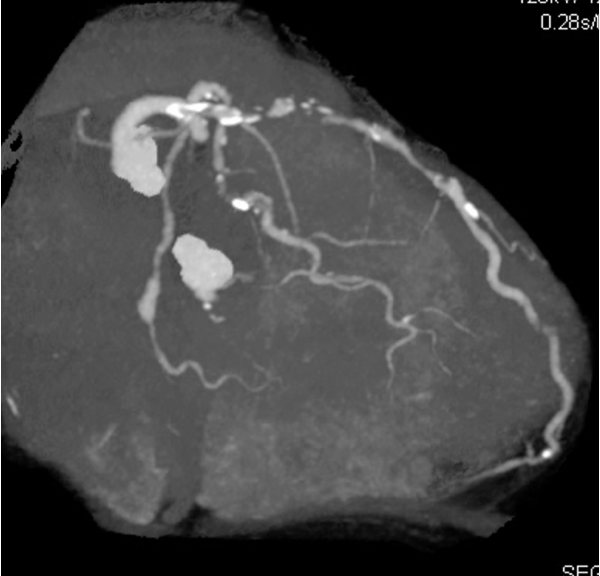

RCA: Seg1)total occlusion, Bypass graft SVG-RCA 99%. LCA:LAD Seg7)total occlusion,LCx Seg12)90%,seg13)90%.seg14)total occlusion, Bypass graft LITA-LAD・FreeRITA-LCX patent, SVG-seg9)occluded.

PCI for the degenerated SVG was determined to be at high risk of distal embolism so we planned to perform PCI for native RCA. Antegrade wire crossing was thought to be difficult (J-CTO score was 3 : calcification, bending and lesion length), therefore we planned retrograde approach via SVG. To avoid ischemia during the retrograde procedure, we dilated the severe stenotic lesion in SVG with small balloon and then micro catheter was advanced. It was very difficult to pass the graft anastomosis, but reverse wire technique at distal RCA was effective. Even after the advancement of both antegrade and retrograde wires, it was also difficult to pass the CTO lesion due to strong bending. Finally, retrograde wire was passed with Reverse CART technique and externalization was achieved. After DES implantation, native RCA was nicely revascularized.